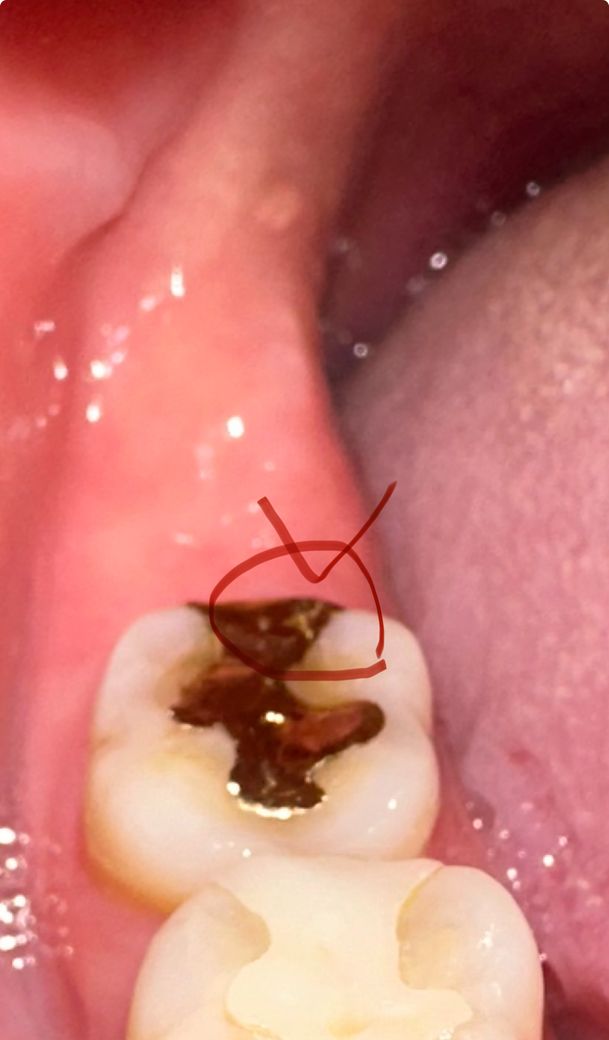

위에 사진이 그 전이고 밑에 사진이 금 간것처럼 보이는 지금 입니다 ㅠㅠ 밑에 사진에 하얗게 선 그어진것처럼 저게 금 간거일까요? 크게 시리거나 통증 있거나 그러진않습니다 원래 저런 선 그어진게 없었는데 갑자기 생겼습니다 ㅠㅠ 뼈 조각 모르고 씹긴했는데 그것때문에 이런걸까요..? 가만히 놔두면 크게 문제가 될까요? ㅜㅜ

• 안녕하세요 치과의사 김철진입니다. 치아가 살짝 깨졋거나 하는경우에 증상이 잇거나 충치가 생긴게 아니라면 크게 신경쓰지 않으셔도 됩니다.

• 사진으로는 정확한 판단이 힘들어 보입니다. 일반적으로 근 그래서 보철물은 파절이 되거나 하진 않고 마모가 되는 경우가 있습니다. 자세한 확인을 위해서 치과에서 진료를 받아보는 것을 권유드립니다

• 사진상으로는 금이 간것으로 판단하기는 어렵습니다. 보다 정확한 상태 확인을 위해 우선 치과에 방문하여 진료를 받고 만약 인레이 파손이 맞는 경우에는 재치료가 필요로 됩니다.